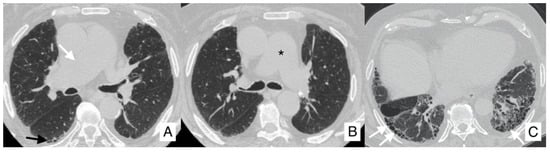

4.4. Pneumothorax